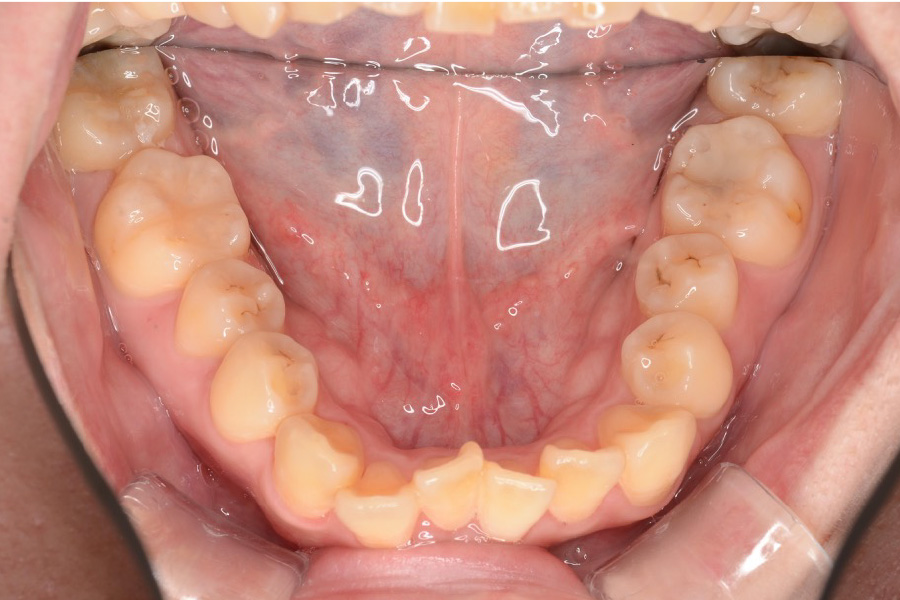

治療前

主訴 全体のガタつきが気になる

治療内容 インビザライン矯正

非抜歯